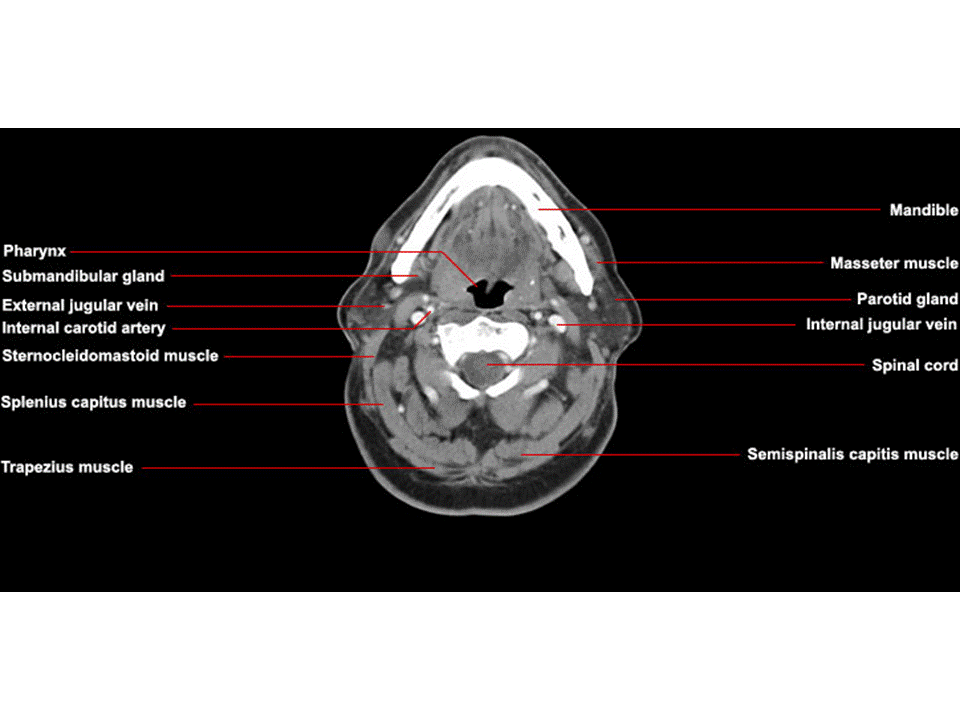

CT Neck Axial Anatomy

CT Neck Axial Anatomy Anatomy Ct Head And Neck Explore the anatomy and pathology of the brain and skull in. Learn the radiological anatomy of the head and neck on a ct scan with axial, coronal, sagittal and 3d images. Learn about the compartments delimited by the deep cervical fascia in the head and neck region, their anatomy, relations and. The materials here serve only as. The case is. Anatomy Ct Head And Neck.